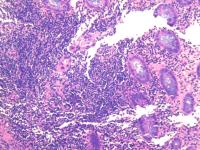

横结肠息肉

性别年龄56临床诊断

一般病史体检

标本名称横结肠息肉

大体所见灰白2粒

肠粘膜息肉。

小灶区域腺上皮有异型,重切一张再看看。

表面黏膜上皮有很少异型细胞。间质中一团上皮样细胞性质不明,没有明显异型性。可描述发报告。